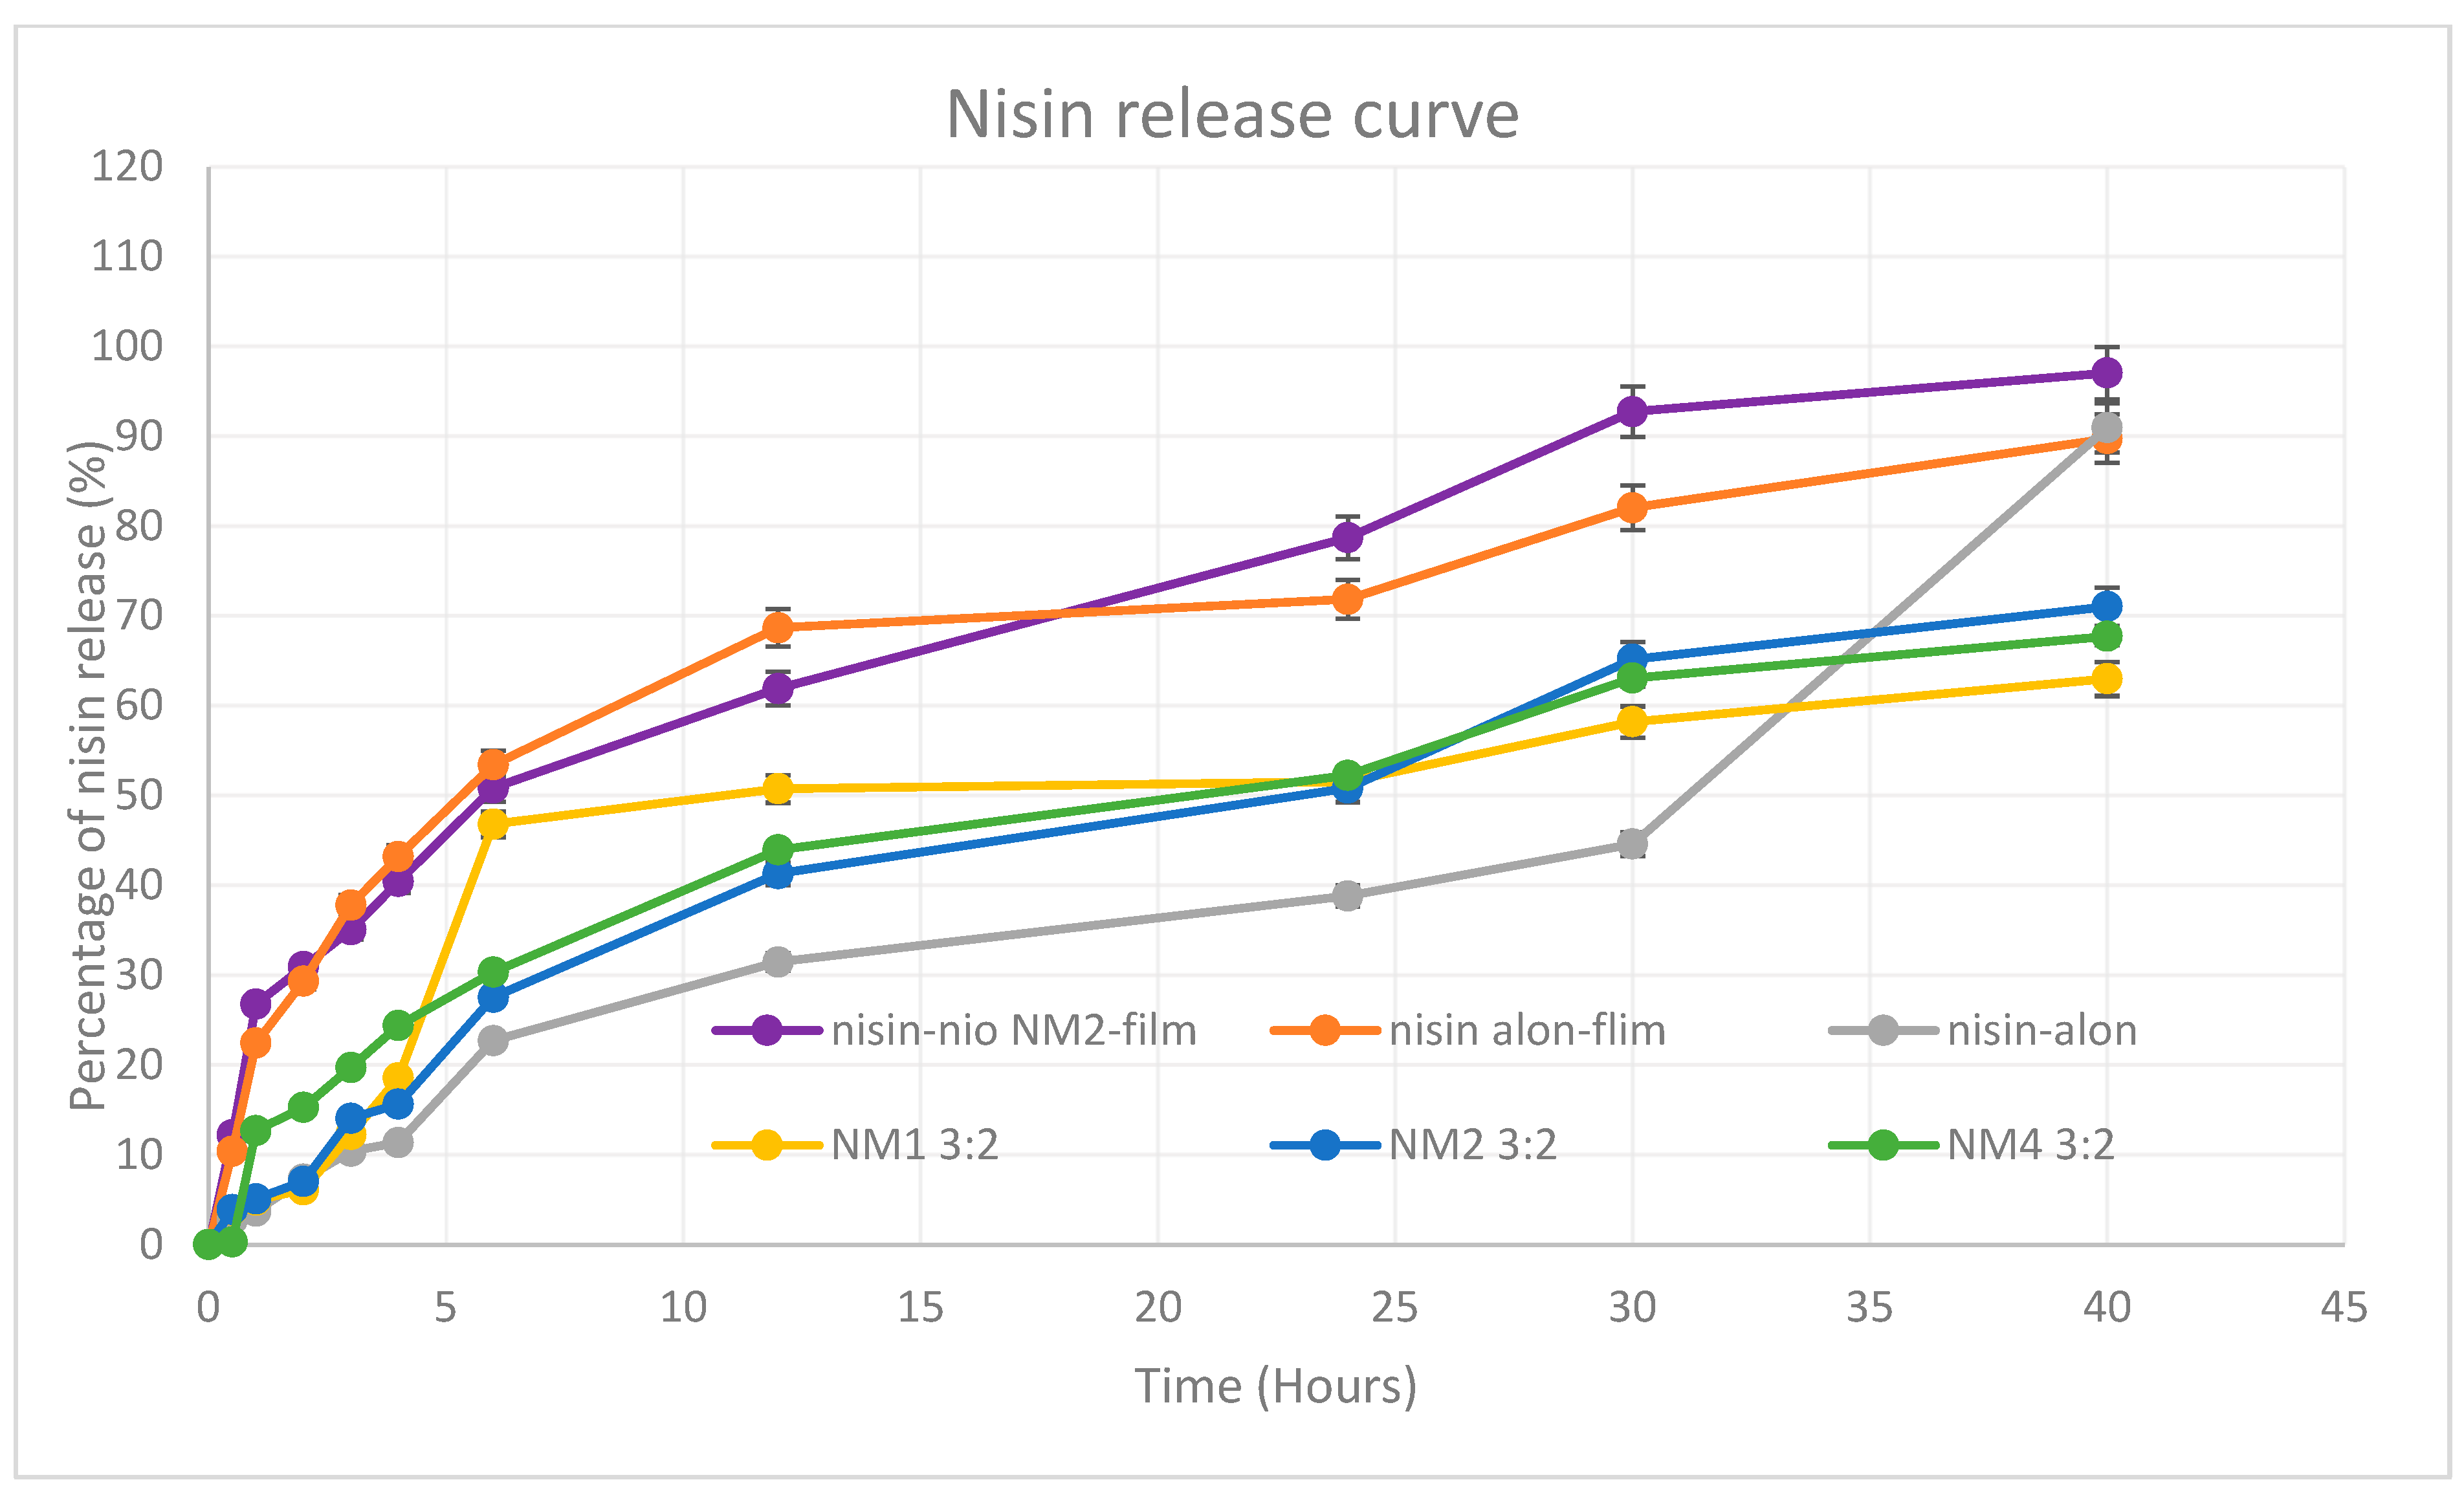

5.9. In Vitro Release Profile

5.10. Kinetic Modelling of Drug Release